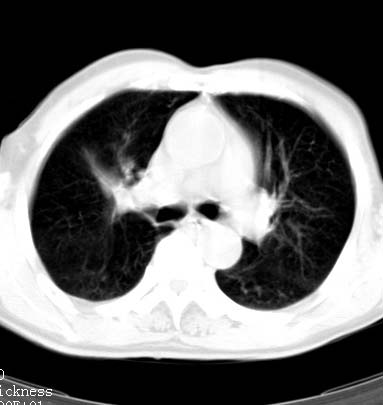

标题: CT14027:男性病人 71岁 咳嗽咳痰数周. [打印本页]

标题: CT14027:男性病人 71岁 咳嗽咳痰数周.

男性病人 71岁 咳嗽咳痰数周.诊断结核应该有保障吧!

右上肺结核,请结合痰检除外活动期;右上叶支气管官腔狭窄建议支气管镜或抗僗后随诊除外堵塞性改变。

高度怀疑肺癌,强烈要求纤支镜检查。

支持双上肺继发性肺结核。